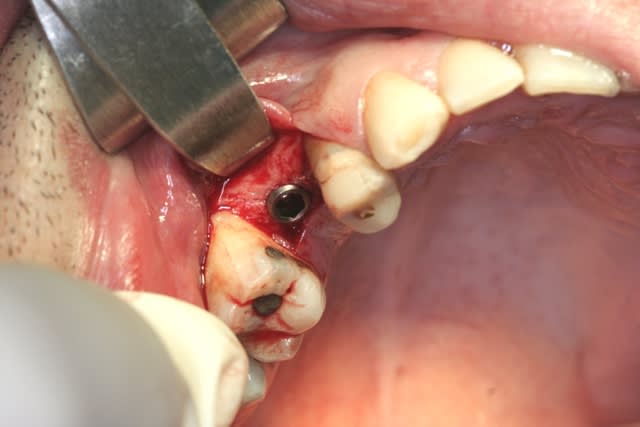

tiens...un ptit cas...

dans ce petit cas...j'ai commencé avec le kit MIS...et fini ma voie crestale avec le kit HBS...

ok, c'est un mini soulevé...mais bon , c'est un exemple...

juste une précision...premier foret 1.3mm sur 8mm...expansion pour mettre un implant de 4x10...

j'ai juste "léché" la préparation du site final avec le foret terminal du système...sur 8mm...avant d'insérer l'implant...stab primaire au top...blocage à 40 Ncm...